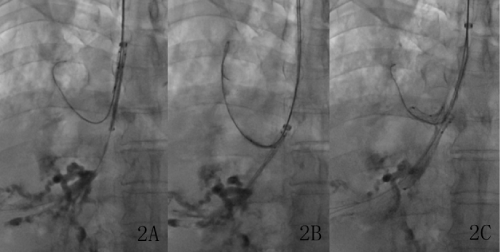

| Figure 2: A) A small Y-shaped airway stent was introduced into the right main bronchus; B) the two branches of the small Y-shaped airway stent were introduced into the right upper bronchus and the right intermediate bronchus; C) the Y-shaped stent was released completely under fluoroscopy |